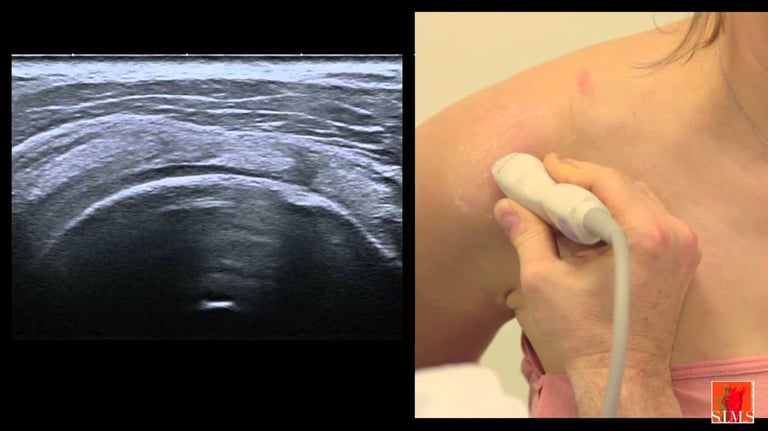

Pathologie de la coiffe des rotateurs

L'épaule et le genou sont deux articulations ou l'on réalise énormément d'arthroscopie, technique mini-invasive sous caméra.